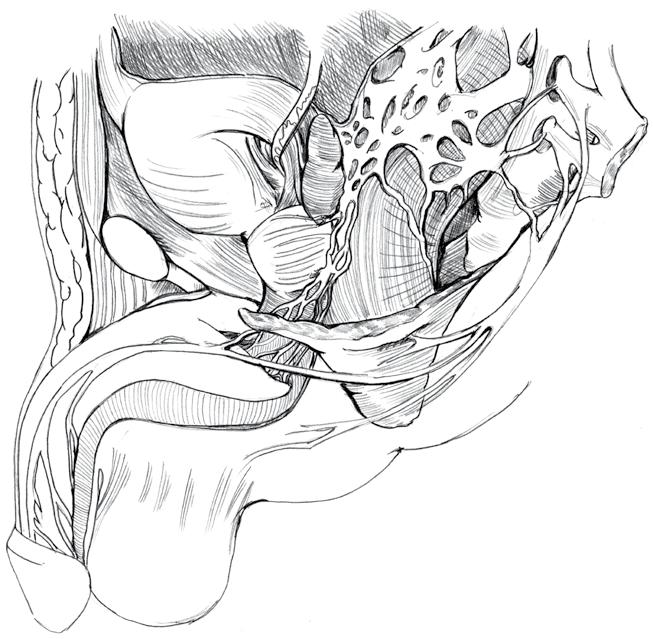

4. Anatomie a fyziologie ženského genitálu ..............

4.1 Anatomie 57

4.1.1 Zevní pohlavní orgány

4.1.2